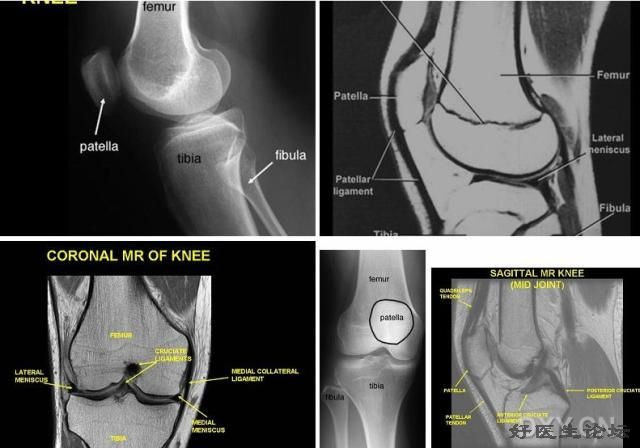

影像学检查

* CT

* MRI

6.jpg

MRI   MRI   MRI